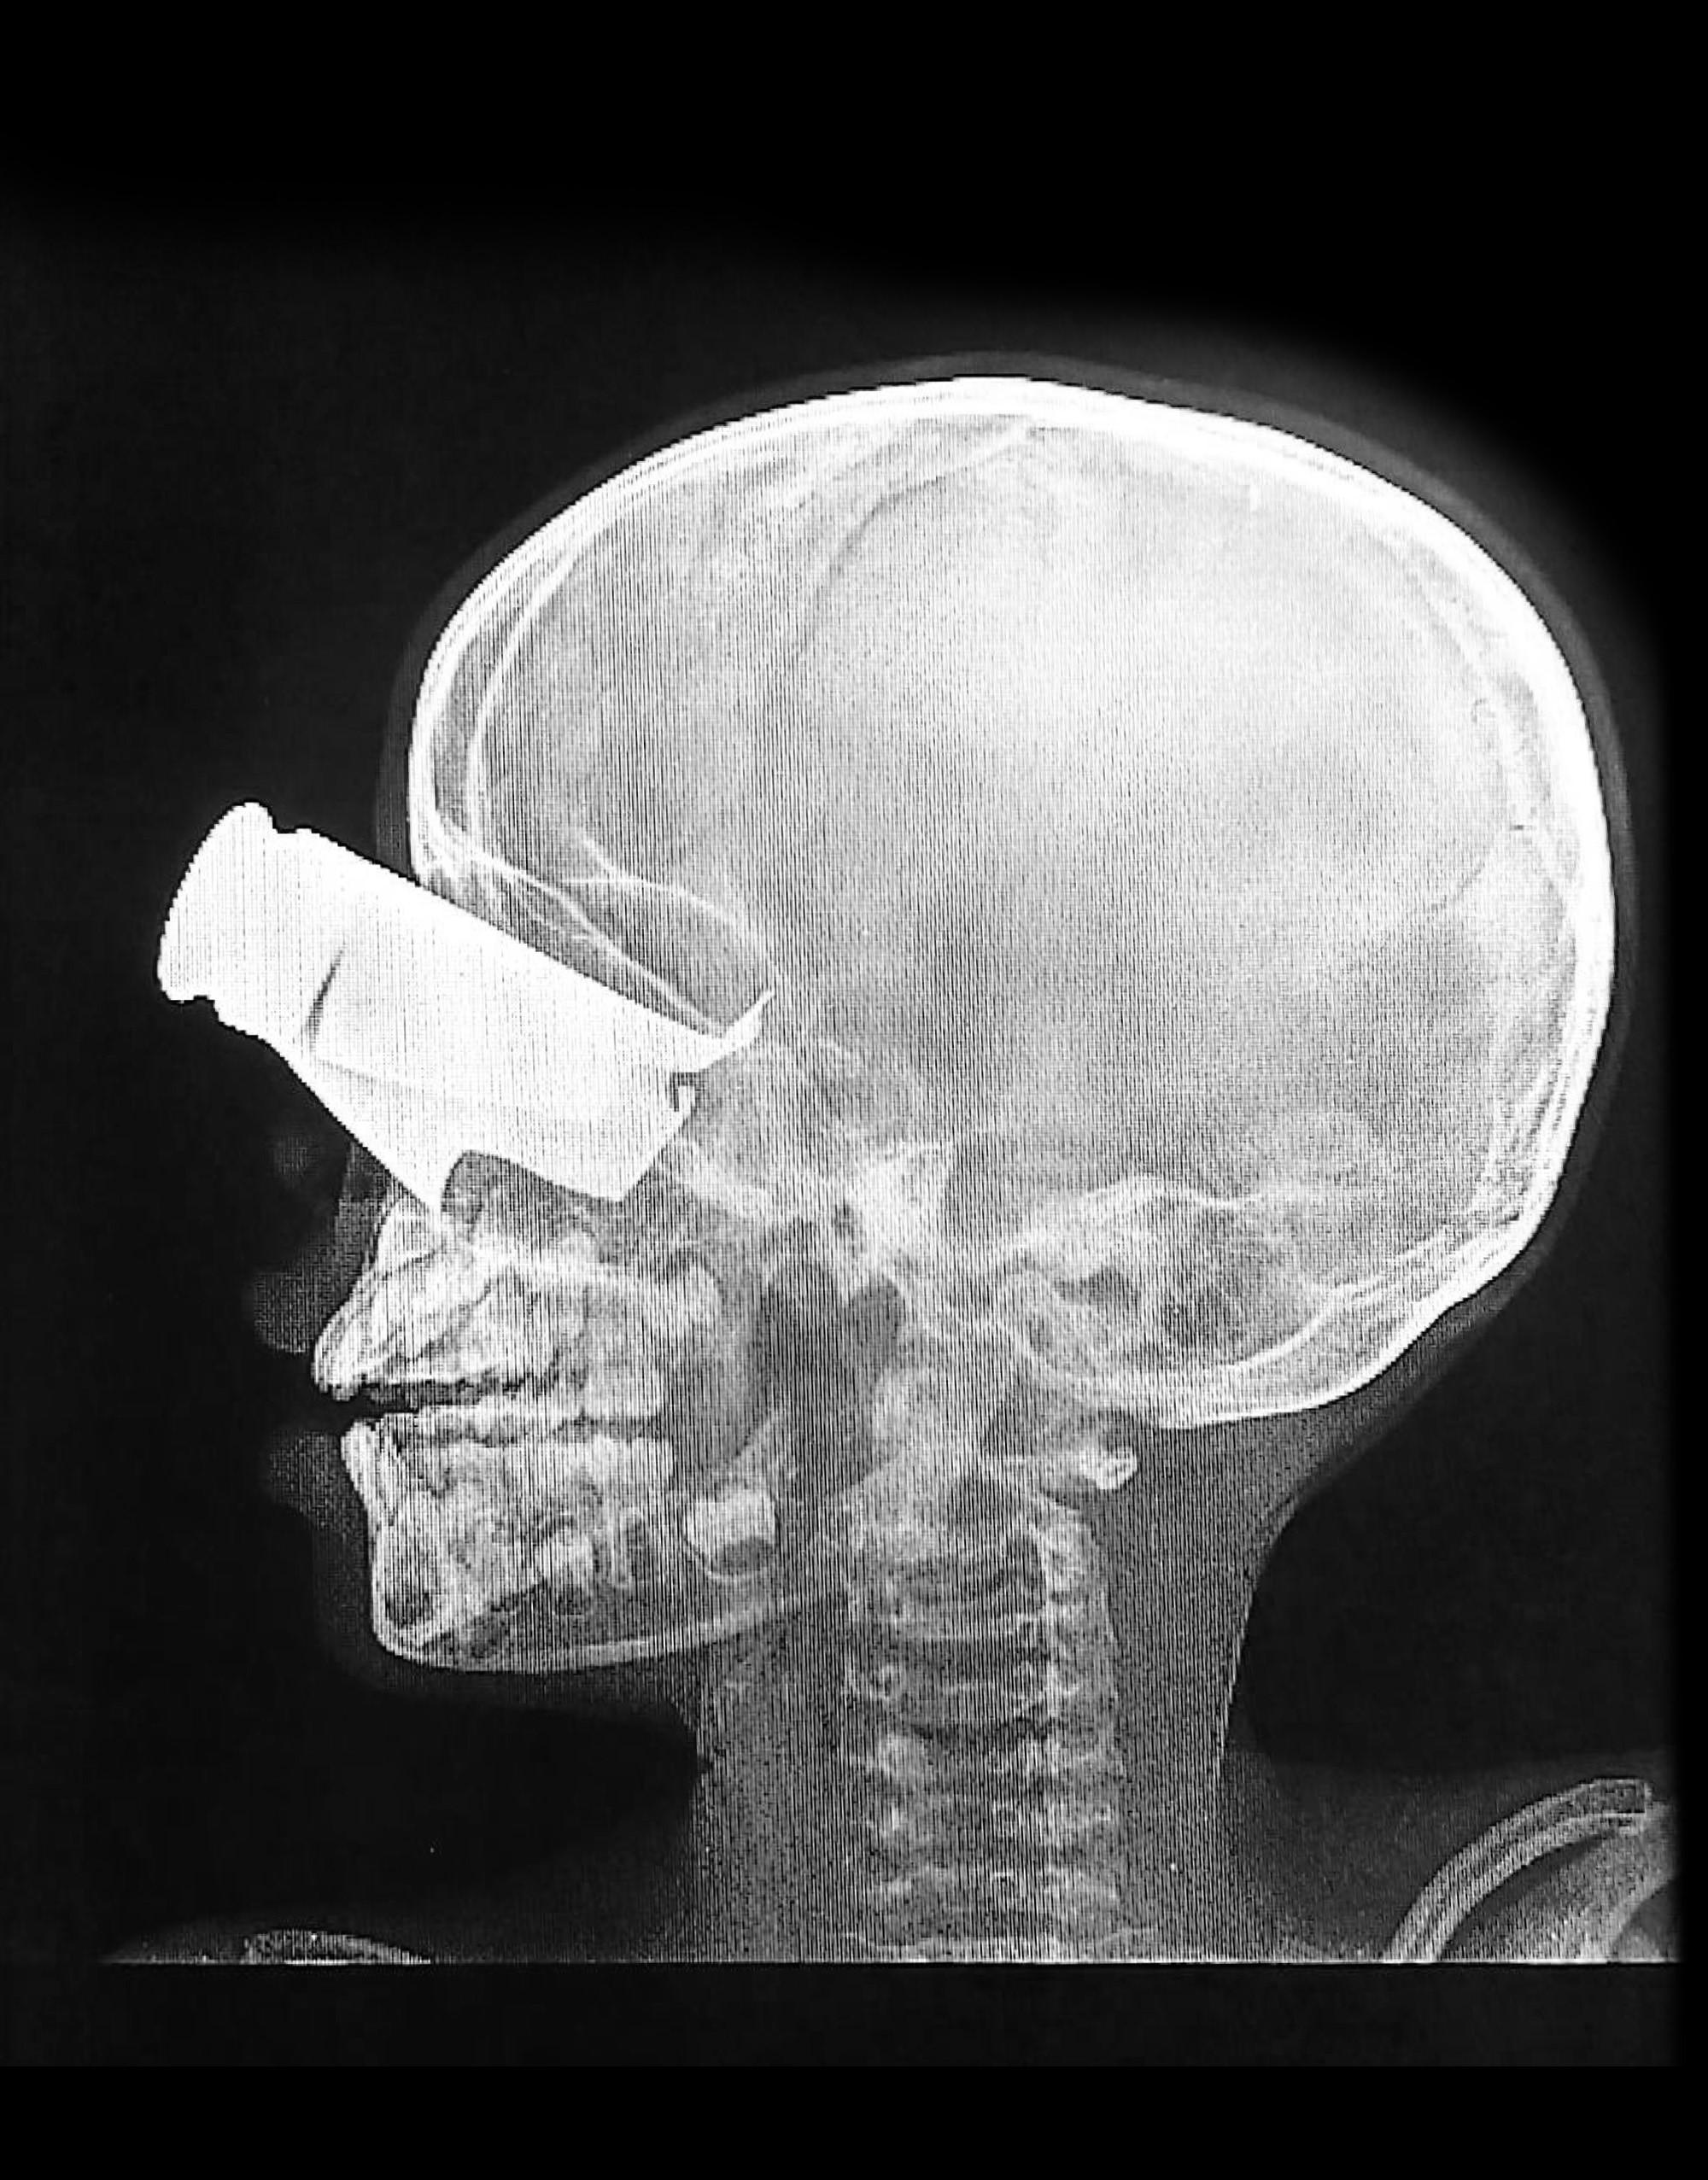

Parmi les patients que nous avons reçus, un garçon de neuf ans est arrivé avec une importante blessure par éclat d'obus à l'œil, des fractures faciales étendues, et deux doigts amputés. Il souffrait énormément et était exposé à la poussière après un long voyage pour atteindre le centre de soins.

Même avec des soins optimaux, il risque de garder des séquelles à long terme. Il a été transféré à N'Djamena pour y recevoir des soins complémentaires ».